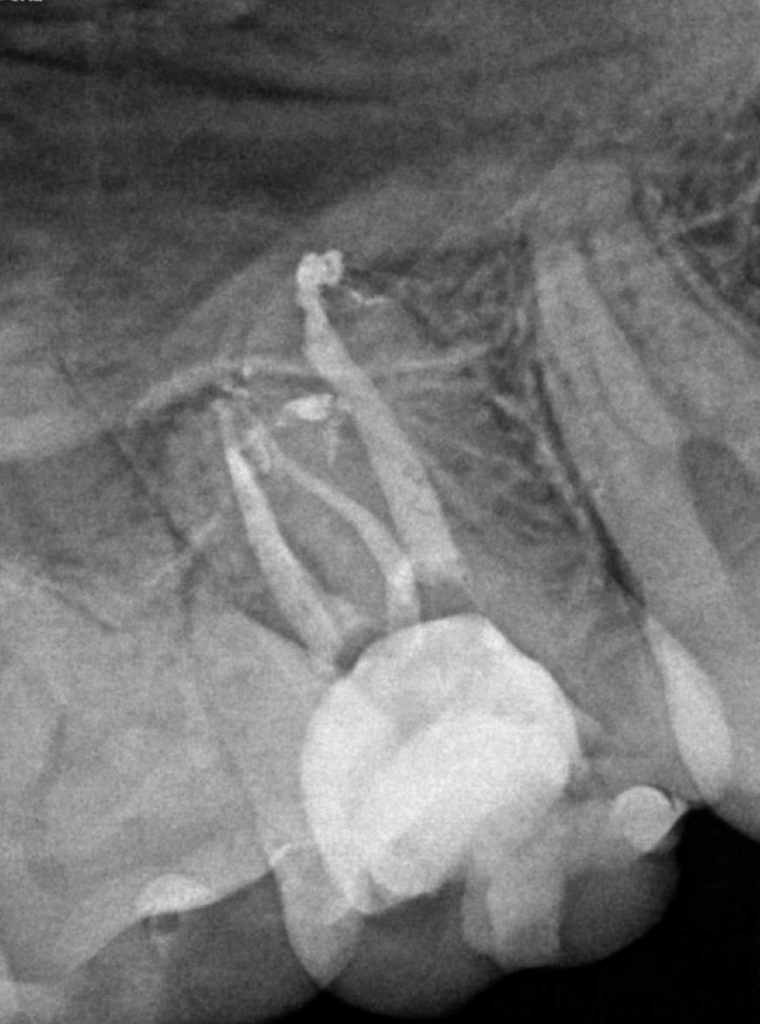

Reco pared vesticular